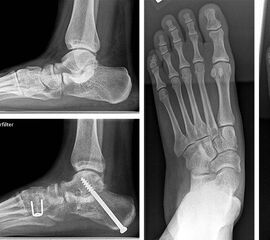

Zum Operationszeitpunkt 11-jähriger Junge mit großer Coalitio talocalcanearis (Längsausdehnung 25 mm, Querausdehnung 15 mm) und ausgeprägter kontrakter Planovalgus-Deformität (a und b). 4 Jahre nach Coalitio-Resektion, Fett-Interposition,

Abbildung 4

Nicht selten ist bei der Coalitio talocalcanealis zusätzlich eine Planovalgusdeformität zu beobachten. Die umfangreiche Literatur der vergangenen Jahrzehnte zur Coalitio beschrieb diese Kombination als prognostisch ungünstig für ein resezierendes Vorgehen, ließ bis vor wenigen Jahren die Frage des Vorgehens in diesen Fällen aber weitgehend offen. Luhmann und Schoenecker 8 berichteten von einem Fall sekundärer Calcaneus-Verlängerungsosteotomie, Hamel beschrieb 2009 die simultane Coalitio-Resektion und Calcaneus-Osteotomie an 9 Patienten im Kindes- und Jugendlichenalter 6 und berichtete später (2012)(Hamel 2012) über mittelfristige Ergebnisse mit Beschwerdefreiheit in 5 von 8 Fällen (Abb. 4); zwei Fälle hatten noch Beschwerden bei intensiver Belastung und in einem Fall mußte eine in-situ-Arthrodese sekundär durchgeführt werden. Blitz (2010) 9 stellte vier Fälle und Mosca und Bevan (2012) 4 zwei Fälle von Coalitio-Resektion und simultaner Calcaneus-Verlängerung vor mit jeweils überwiegend guten Ergebnissen. Giannini et al 10 berichteten über gute Ergebnisse nach Resektion und Einbringung eines Sinus-tarsi-Spacers zur Stellungskorrektur.

Operatives Vorgehen: Nach Resektion der Coalitio (s.o.) wird über eine schräge Hautinzision über der lateralen Fußwurzel unter Schonung der Suralis-Äste und der Peronealsehnen der vordere Calcaneusabschnitt subperiostal umfahren. Nach Anbringen eines Distraktors erfolgt eine Osteotomie etwa 8 mm distal der vorderen Begrenzung der Gelenkfläche der hinteren Kammer des Subtalargelenkes. Hier wird je nach Ausmaß der Deformität ein trikortikaler Keil von ca. bis zu 5 bis 8 mm Basisbreite aus dem vorderen Beckenkamm eingebracht. Eine Sicherung des Calcaneocuboidgelenkes wie früher bei wesentlich ausgedehnteren Verlängerungen empfohlen erscheint nicht erforderlich. Die Rückfußvalgus-Komponente wird über eine separate Inzision im Bereich des lateralen Tuber calcanei durch medialisierende Osteotomie korrigiert. Im Kindes- und Jugendlichenalter ist eine Osteosynthese mit zwei perkutan von der Ferse aus eingebrachten Kirschner-Drähten ausreichend, wobei beide Drähte beide Calcaneus-Osteotomien stabilisieren. In aller Regel wird dann ein zweiter trikorticaler Span (ca. 5 mm Basisbreite) über einen dorsalen Zugang im Bereich des Os cuneiforme mediale in open-wedge-Technik zur Plantarisierung des medialen Strahles eingebracht. Hier ist eine Osteosynthese oft nicht erforderlich.